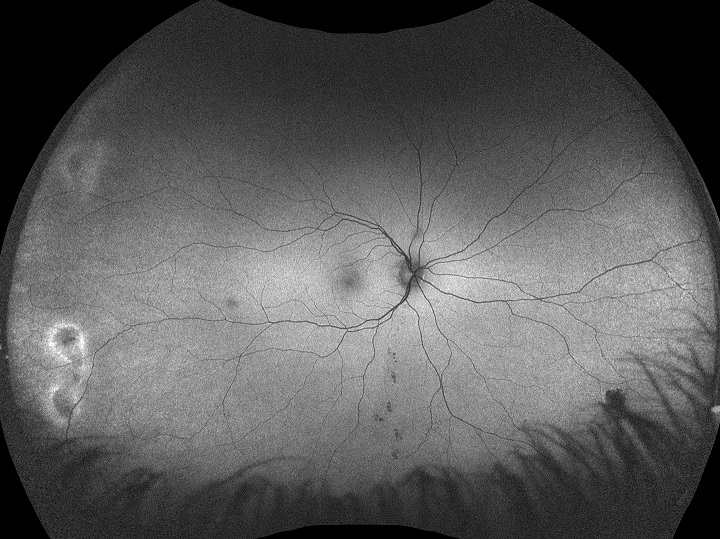

Monaco est une nouvelle approche intéressante pour améliorer votre examen clinique. Seul appareil d’imagerie de la rétine ultra-grand champ à posséder un SD-OCT intégré, Monaco produit une image optomap® à 200° en une seule prise en moins d’½ seconde ainsi que des vues transversales OCT à 40° des structures de la rétine. Monaco permet d’obtenir rapidement une image en plusieurs modalités avec balayages couleur, autofluorescence et OCT, pour les deux yeux, en seulement 90 secondes.

- Les images optomap et les balayages OCT sont corrélés afin de faciliter l’examen des pathologies.

- Les images Couleur, AF et OCT sont présentées ensemble dans une même vue.